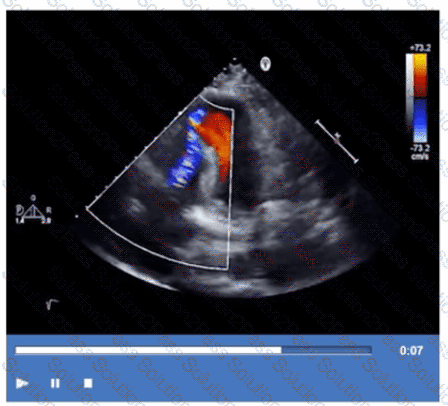

Which type of defect can be seen in this video clip?